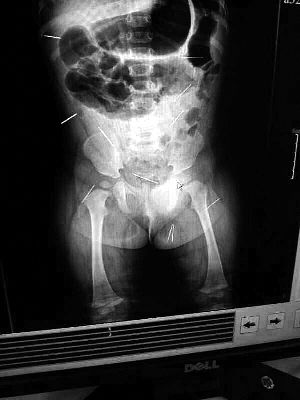

山東聊城11個月女嬰萱萱(化名)疑似被人以12根鋼針插滿臀部、腹腔等部位,昨天在兒童醫(yī)院會診后,醫(yī)生稱3根針靠近胸腔最危險,首批先行取出,預(yù)計將在下周二手術(shù)。孩子父母稱孩子一直由家人照顧,自家與他人并無冤怨。山東警方表示正在偵破中,不便透露案情。

“要不是當(dāng)初那幾個紅點,可能到現(xiàn)在我們還不知道孩子身體里有鋼針!”昨天,在兒童醫(yī)院住院處,萱萱爸爸范先生稱,日前原本很愛笑的萱萱突然變得有些焦躁,一抱起來就哭,孩子母親偶然間在萱萱屁股上發(fā)現(xiàn)了幾個小紅點兒,原以為是蚊蟲叮咬,就醫(yī)結(jié)果卻讓人不寒而栗?!搬t(yī)院拍出的片子上,萱萱的體內(nèi)有12根鋼針,插滿臀部、腹腔、骨盆等各個部位?!狈断壬榻B,因為鋼針已深入體內(nèi),要是孩子不哭鬧,他們很難發(fā)現(xiàn)。

北京晨報記者了解到,目前體內(nèi)的12根鋼針多分布在孩子的臀部,一根在腹部,其余3根在胸腔附近,其中一根很接近心臟?!耙驗楹⒆犹?,醫(yī)生們害怕取針的時候?qū)λ斐蓚?,在胸腔附近?針可能會威脅她的生命”。

截至昨晚6時許,北京晨報記者從兒童醫(yī)院宣傳部門了解到,孩子目前已經(jīng)接受完專家會診,暫定今天和下周一進行術(shù)前檢查,如果一切順利將在下周二手術(shù),“孩子暫時沒有生命危險”。